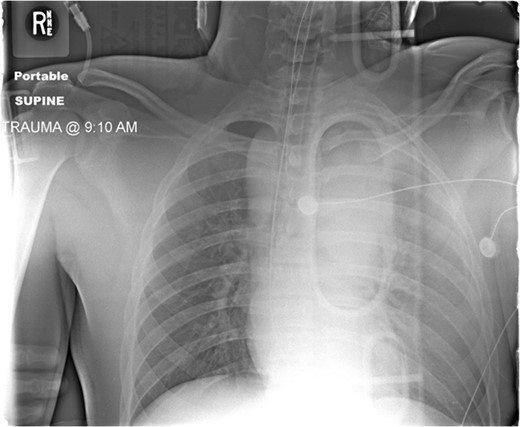

Admission AP CXR demonstrating a widened mediastinum and increased haziness of the left hemi-thorax.